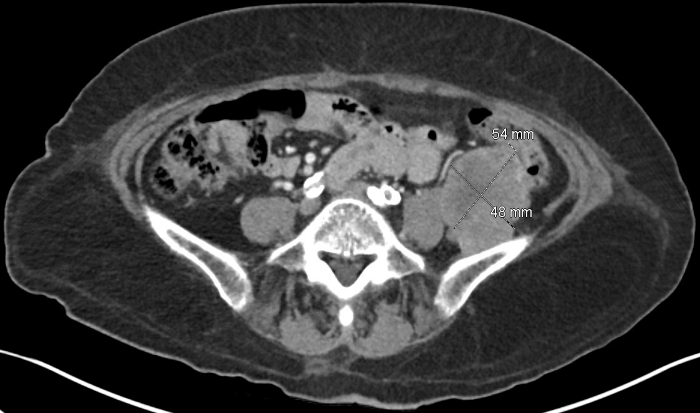

A 70 year old female with stage II hypertension, controlled type 2 diabetes, chronic hepatitis B, previously treated hepatitis C, benign right thyroid nodule, and small cell lung cancer (SCLC) in remission presented to the emergency room with 5 days of severe fatigue and hyperglycemia. Blood pressure (BP) was elevated to 201/123. Exam was notable for facial hyperpigmentation and right supraclavicular fullness. Labs showed hyperglycemia, hypokalemia, metabolic alkalosis, and leukocytosis. She was admitted for further evaluation. A prior colonoscopy had shown an ileocecal tubulovillous adenoma that could not be resected. Given this, she had a CT torso which showed increased size of her known right thyroid nodule, two new left adrenal nodules, and likely retroperitoneal metastatic disease.